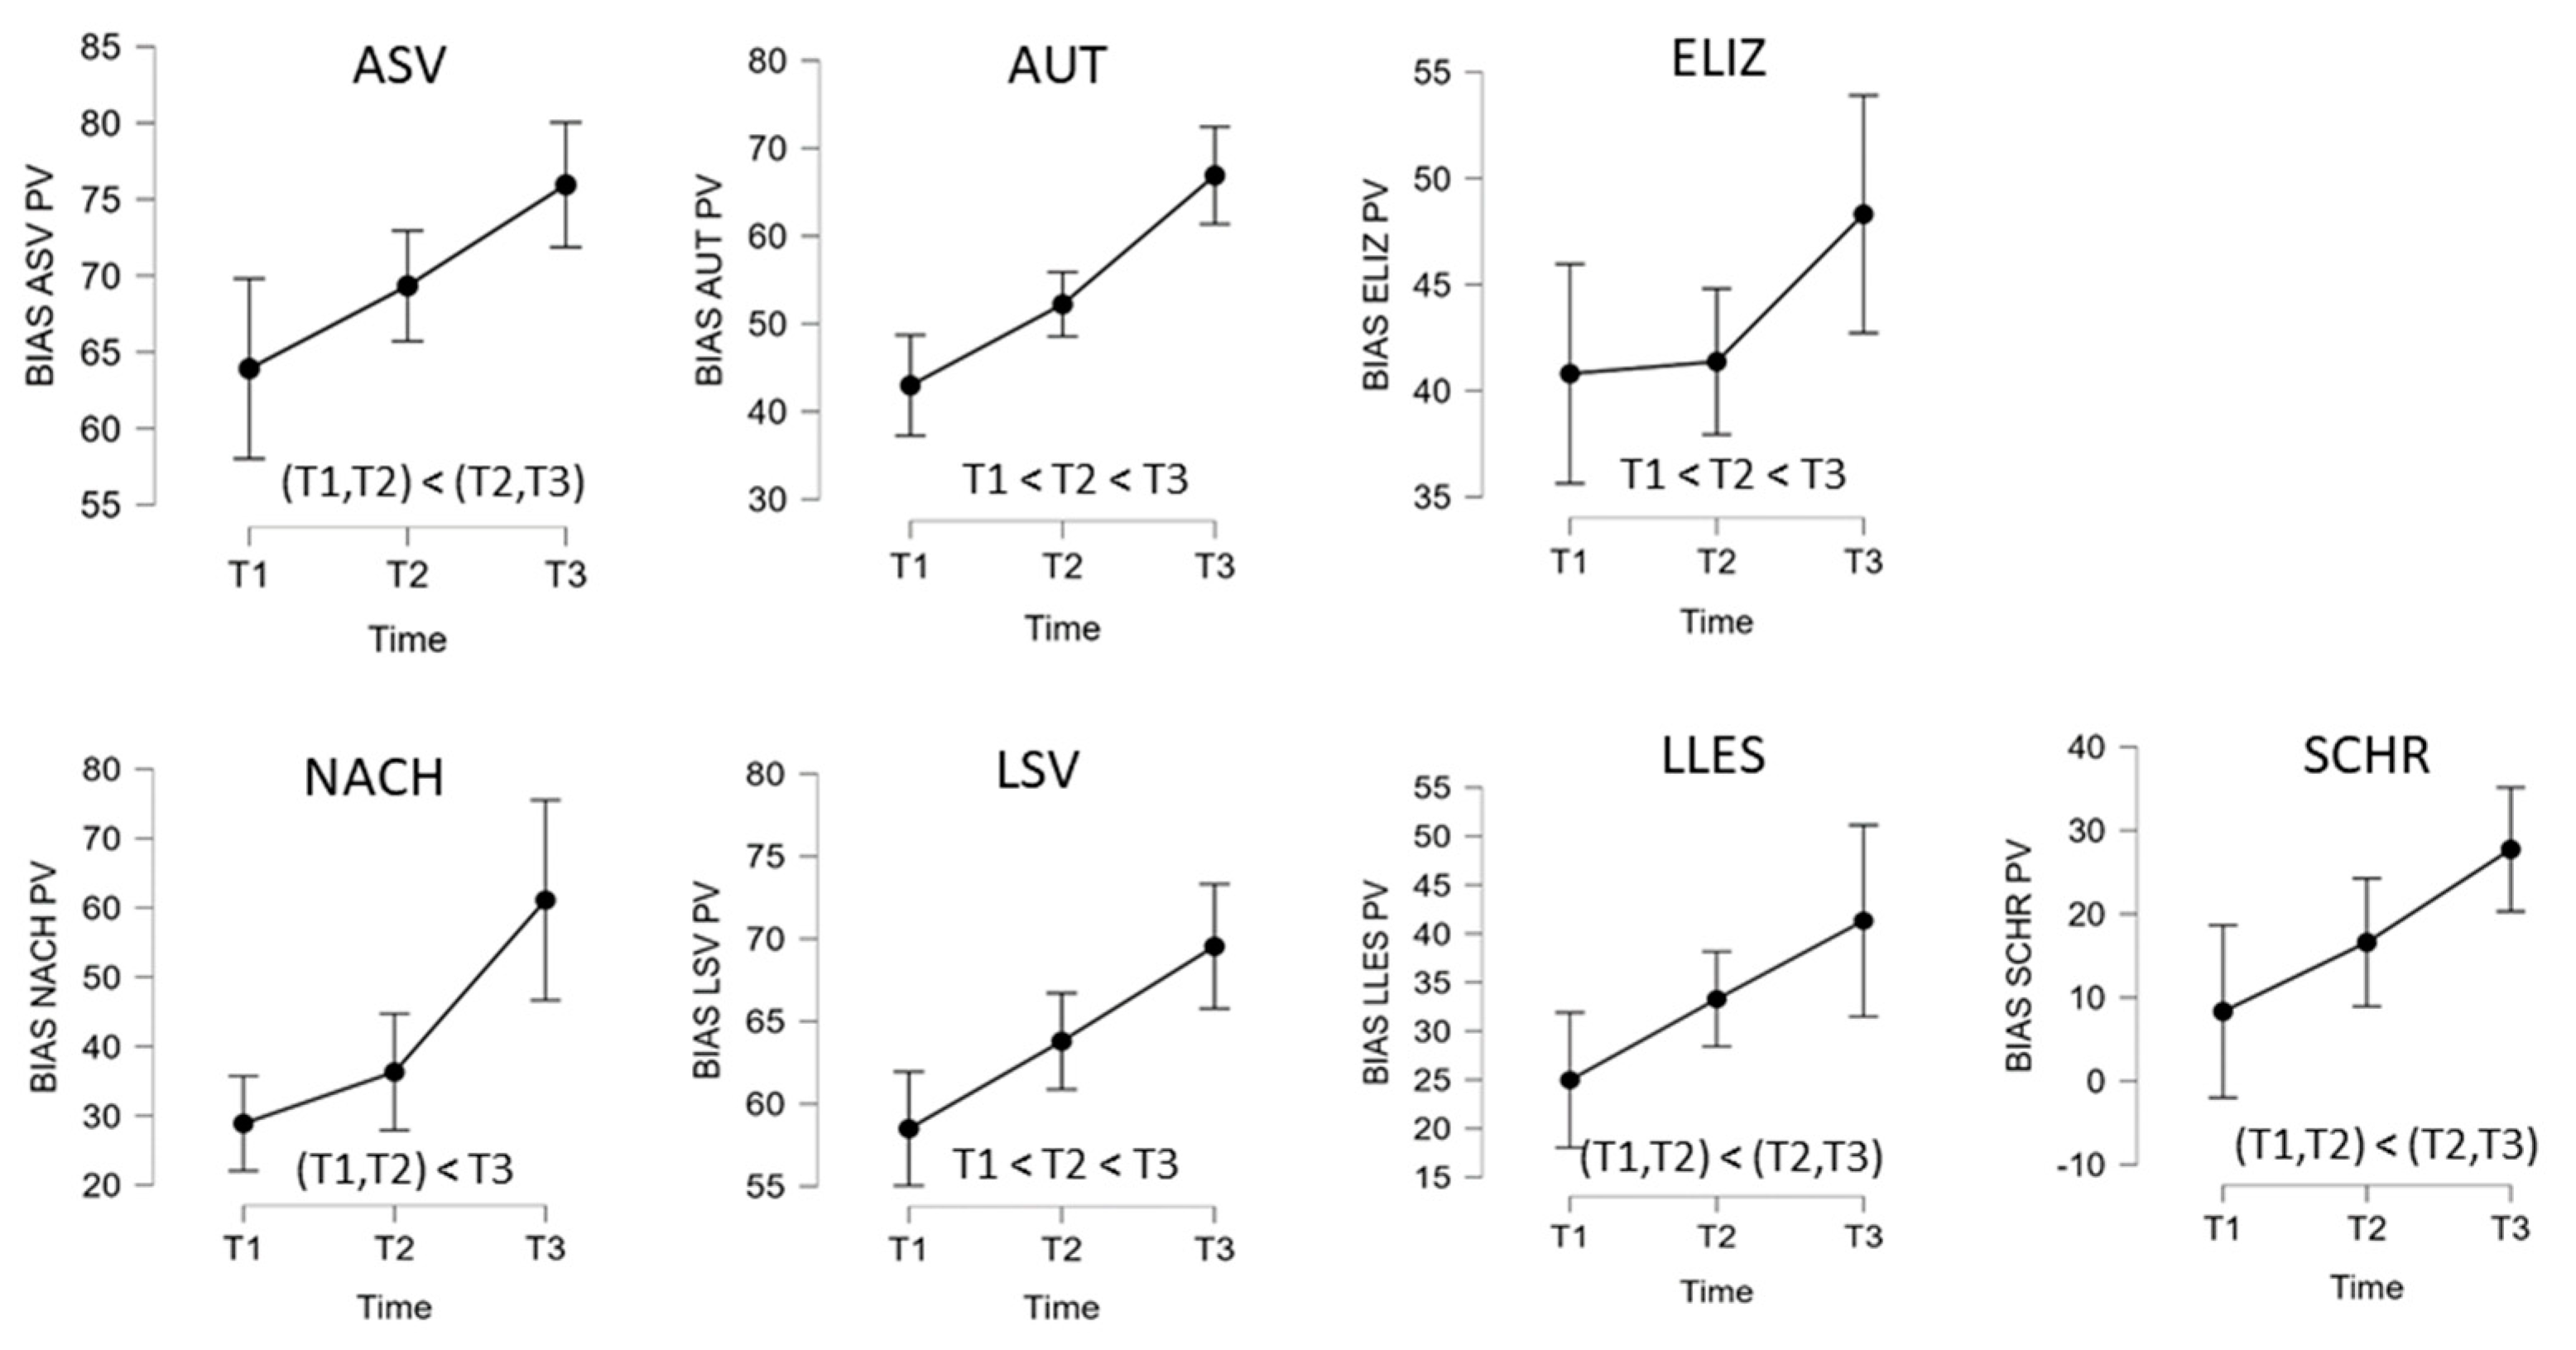

| B | BIAS-R | T1 | T2 | T3 | ANOVA Factor Time | Post Hoc Compar. § | ||

| (n = 10) | M (SD) | M (SD) | M (SD) | F(2,18) # | p | η2p | ||

| Profile level (T-norm) | 37.40 (3.81) | 39.35 (2.97) | 42.35 (2.45) | 35.55 | <0.001 | 0.80 | T1 < T2 < T3 | |

| ASV | Auditory comprehension | 63.91 (12.57) | 69.33 (11.26) | 75.95 (9.35) | 8.64 | 0.002 | 0.49 | (T1,T2) < (T2,T3) |

| AUT | Automated sequences | 42.98 (15.98) | 52.22 (18.39) | 66.90 (17.86) | 29.02 | <0.001 | 0.76 | T1 < T2 < T3 |

| ELIZ | Confrontation naming | 40.80 (6.94) | 41.37 (7.11) | 48.31 (6.31) | 3.85 | 0.041 | 0.30 | (T1,T2,T3) |

| NACH (n = 9) | Repetition | 28.88 (25.39) | 36.30 (26.12) | 61.09 (23.57) | 13.92 | <0.001 | 0.64 | (T1,T2) < T3 |

| LSV | Reading comprehension | 58.49 (18.94) | 63.79 (20.00) | 69.54 (19.59) | 17.24 | <0.001 | 0.66 | T1 < T2 < T3 |

| LLES | Reading aloud | 24.97 (26.14) | 33.28 (24.01) | 41.32 (27.51) | 6.09 | 0.010 | 0.40 | (T1,T2) < (T2,T3) |

| SCHR | Written language | 8.33 (12.35) | 16.60 (19.80) | 27.73 (22.83) | 6.61 | 0.007 | 0.42 | (T1,T2) < (T2,T3) |